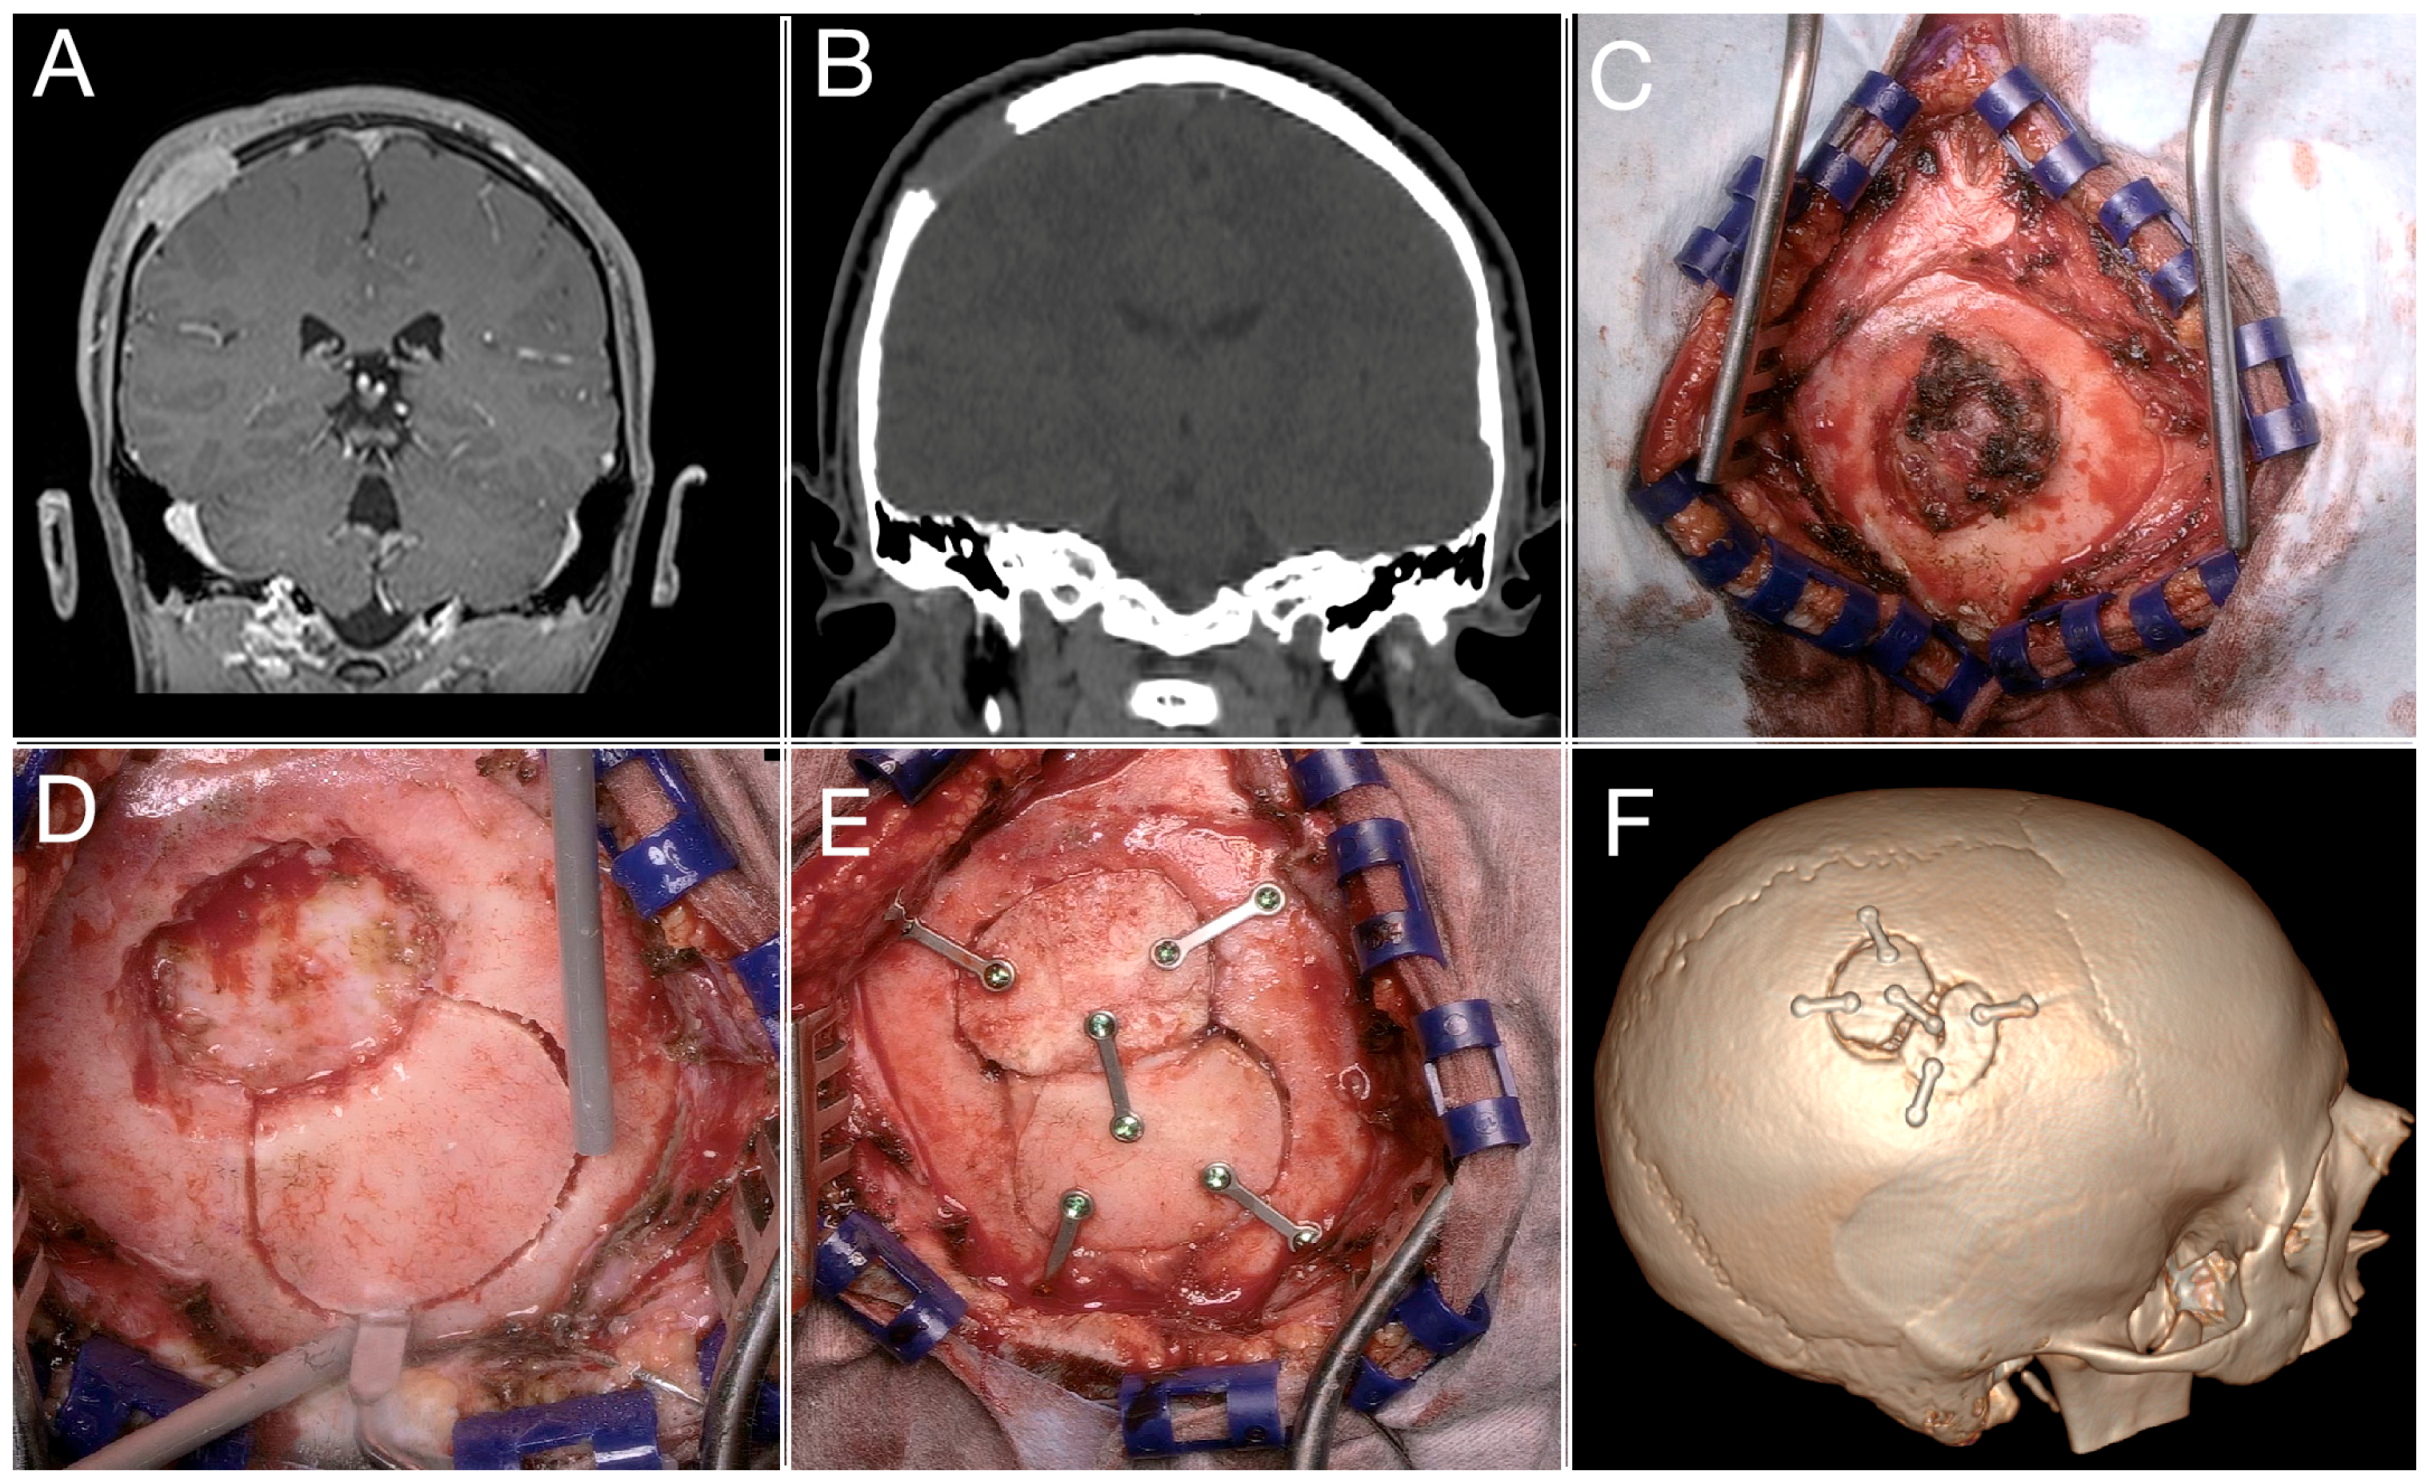

3.3. A Complex Case: Melanocytic Neuroectodermal Tumor